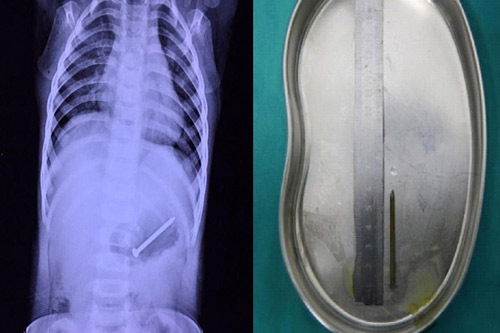

Kết quả chụp X-quang ở bệnh viện cho thấy quả thực chiếc đinh 5cm đã nằm trọn trong ổ bụng của em bé 12 tháng tuổi. Gia đình em lúc này mới hoảng hốt đưa cậu bé đến một bệnh viện lớn ở Quảng Đông, nơi có đủ điều kiện để tiến hành lấy chiếc đinh ra.

Chiếc đinh dài 5cm nằm trọn trong ổ bụng em bé 12 tháng tuổi.

Tuy nhiên, đến khi gia đình đưa được em bé đến bệnh viện, kết quả chụp X-quang một lần nữa cho thấy chiếc đinh đã chuyển vị trí tiến vào sâu hơn trong bụng em bé, khó có thể lấy ra bằng phương pháp nội soi thông thường.

Em bé 12 tháng sau đó phải trải qua một cuộc phẫu thuật bụng kéo dài hơn 1 tiếng đồng hồ. May mắn, chiếc đinh đã được lấy ra khi chưa đâm thủng dạ dày và ruột.